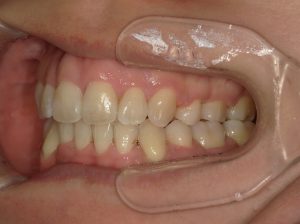

治療前→治療後(右側方)

治療前→治療後(左側方)